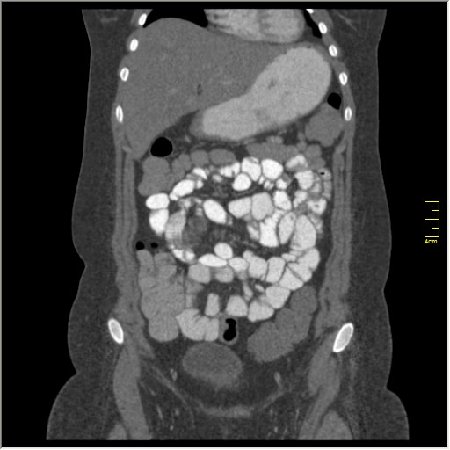

КТ энтерография

Демонстрационные изображение, оцените возможности метода! Толщина среза реконструкции 0.5-1 мм.